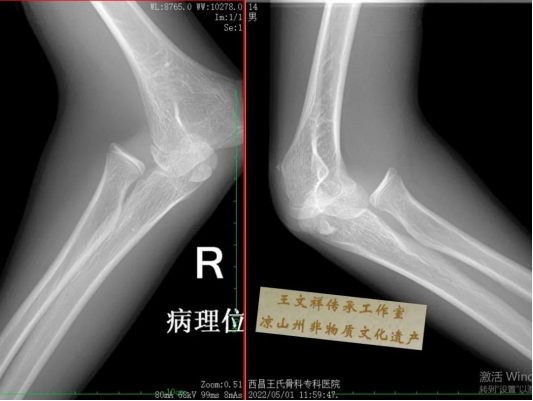

手法复位病例一:14岁,肘关节脱位伴骨折

image.png image.png

复位前                                         复位后